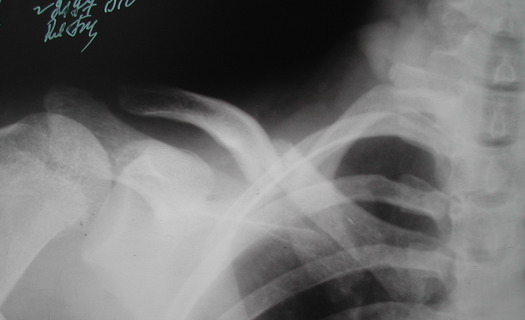

В приложении проект наших тезисов на съезд и клинический пример: Пациентка 23 лет поле неэффективного оперативного лечения (4 нед.) перелома ключицы спицей (была оперирована в С-Петербурге)(снимок после удаления спицы) и результат закрытого БИОС..